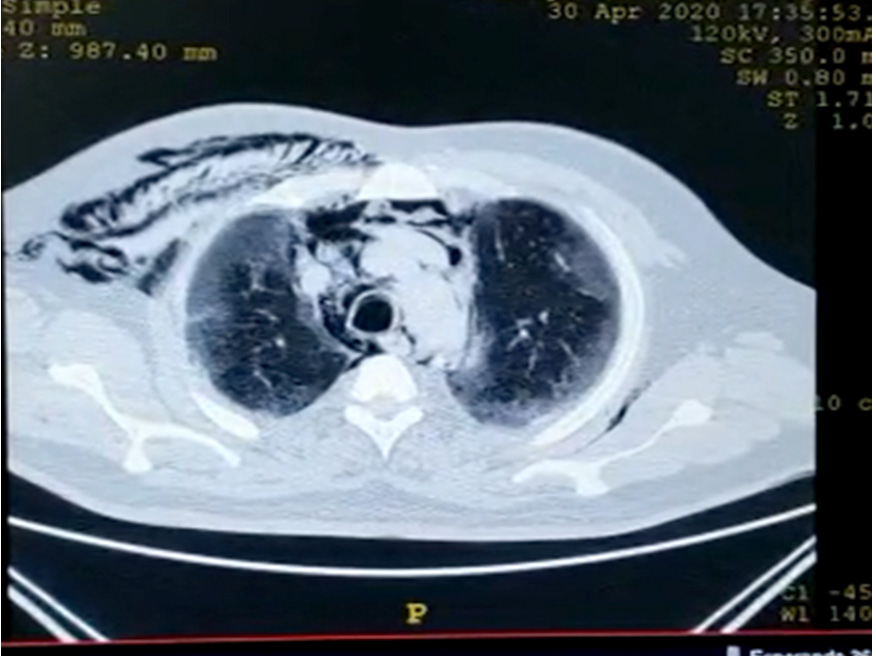

Imaging: an urgent chest computed tomogra- phy was requested and showed subcutaneous emphysema (Figure 1), bilateral ground-glass opacities with peripheral distribution, also air into the hilum and pericardic pleura (Figure 2).